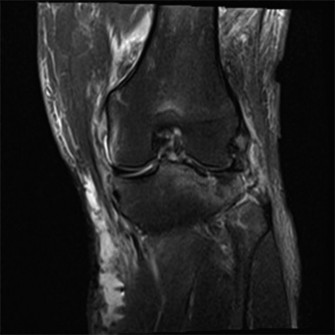

A 20-year-old, male, college football player tackled a fellow teammate in practice and had subsequent pain an…